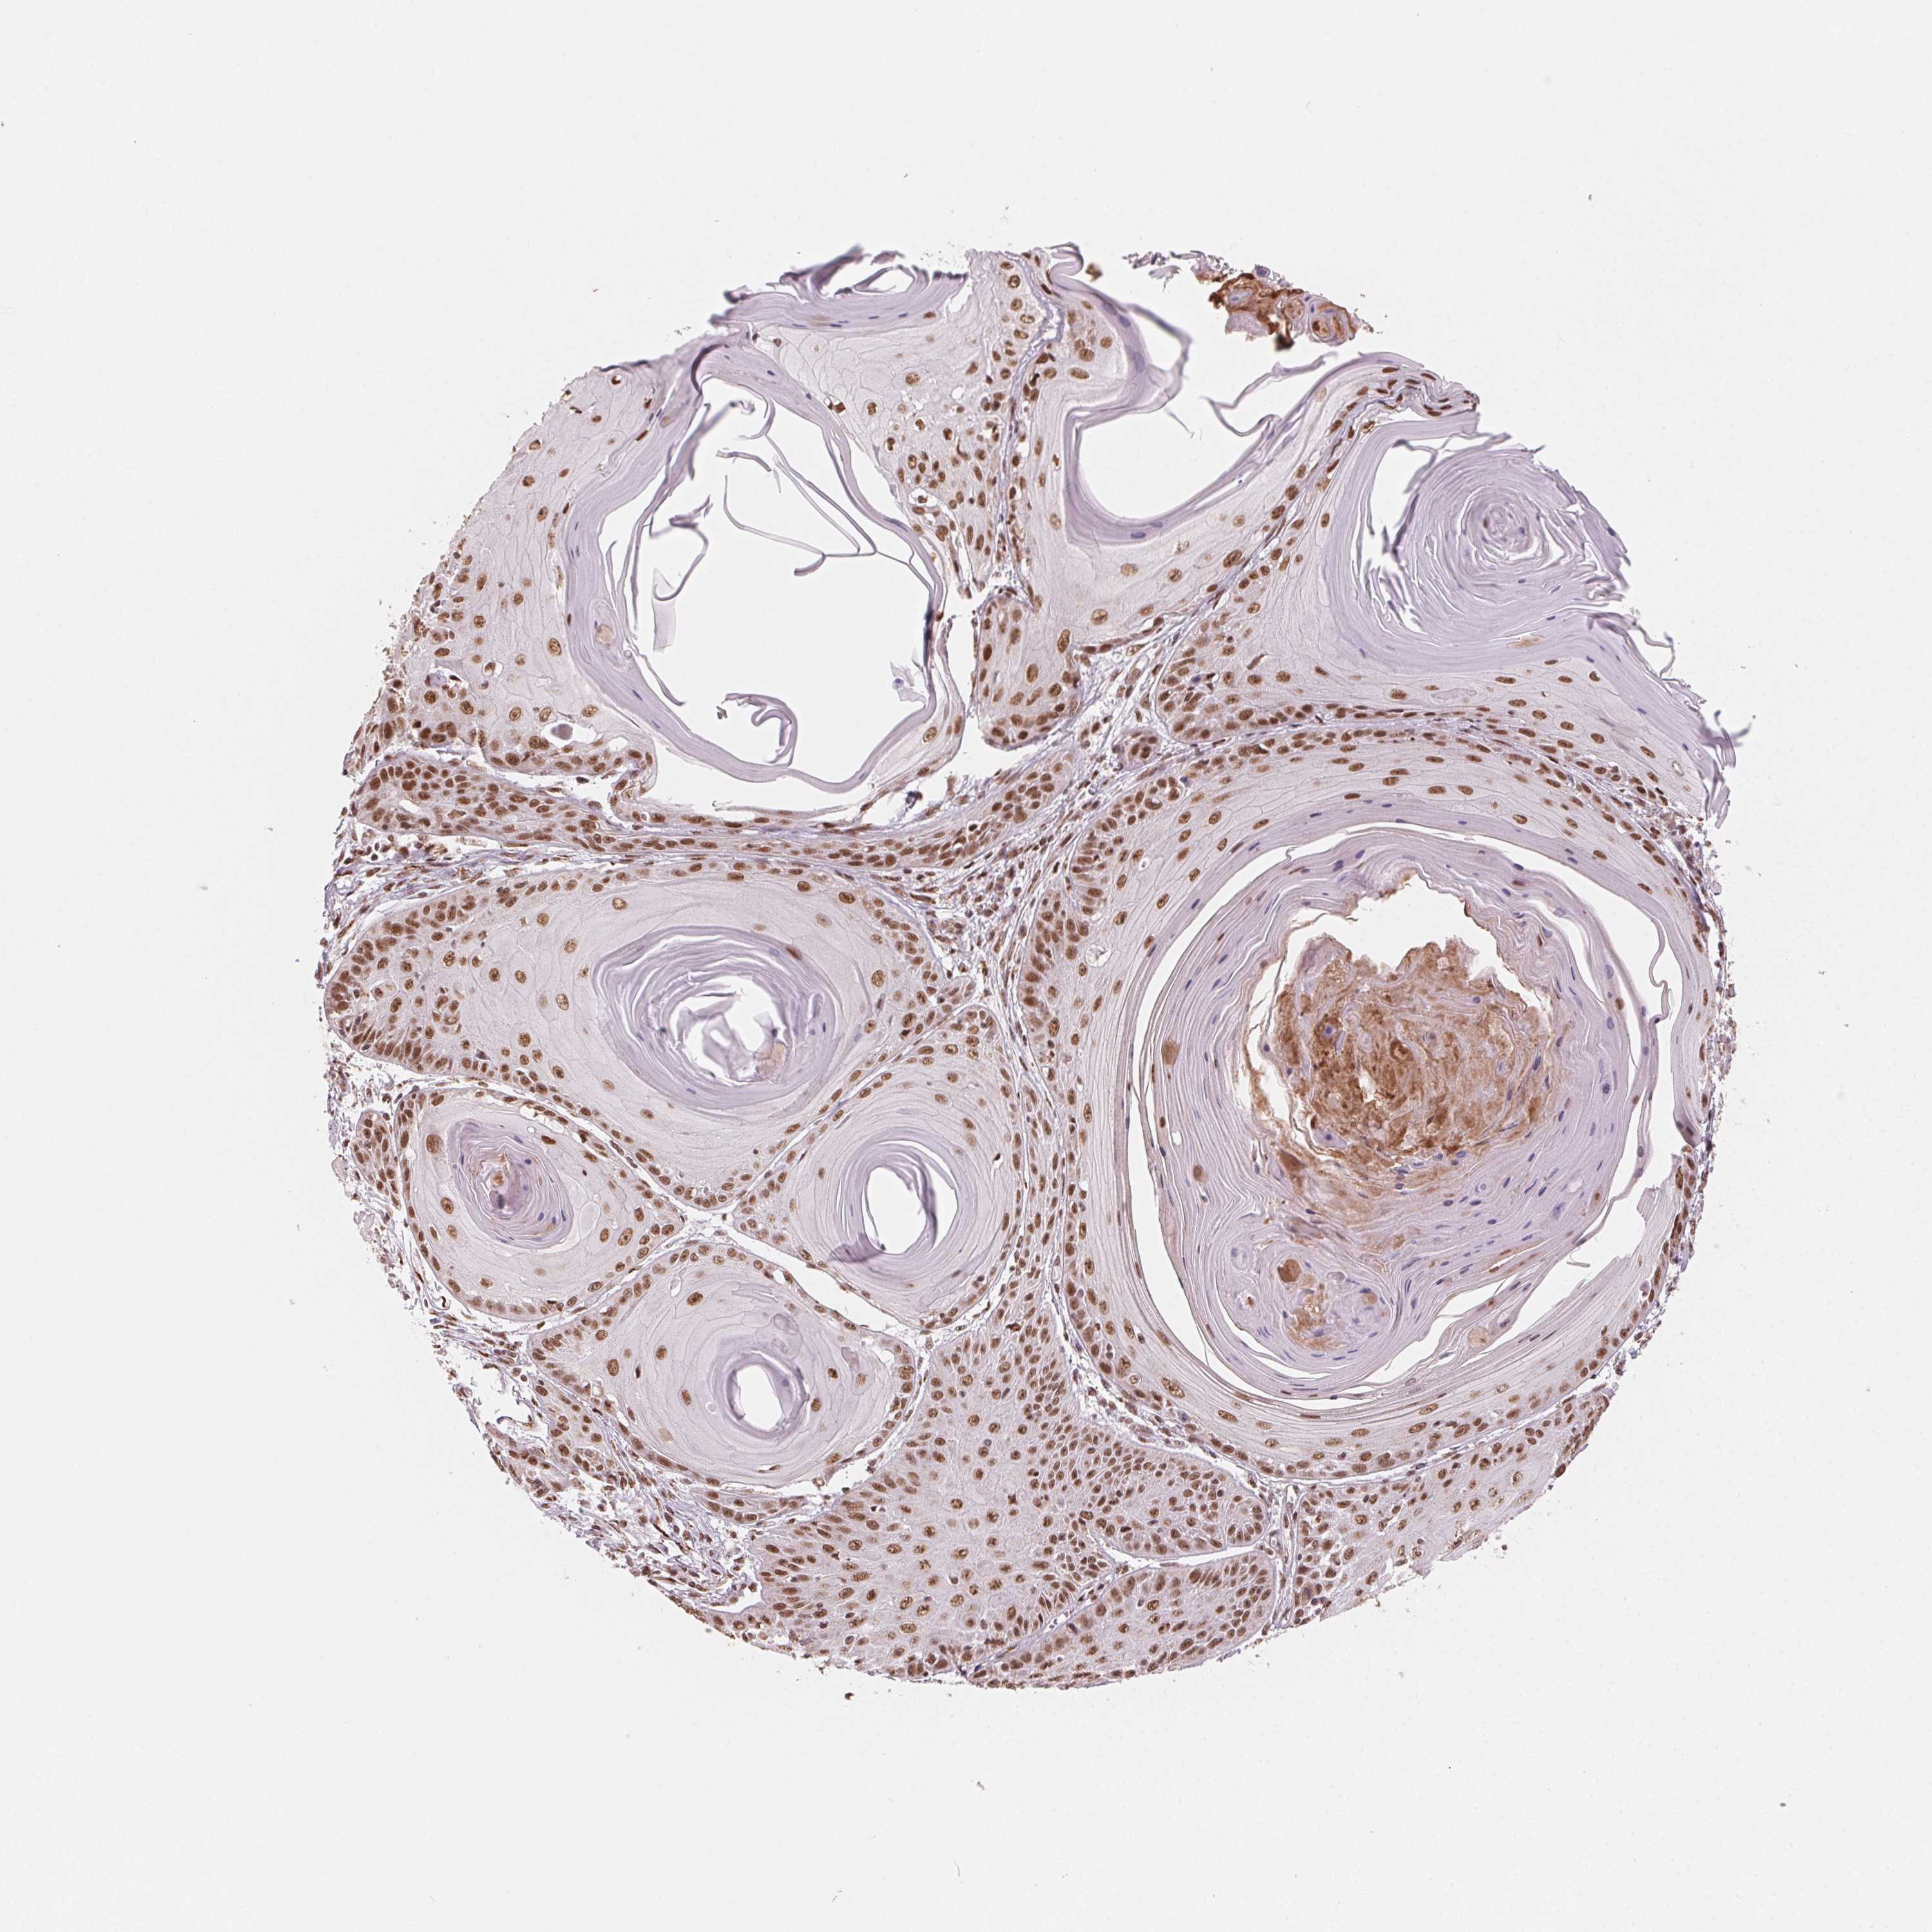

SKIN CANCER - Protein expressioni

A mouse-over function shows sample information and annotation data. Click on an image to view it in a full screen mode. Samples can be filtered based on level of antibody staining by selecting one or several of the following categories: high, medium, low and not detected. The assay and annotation is described here.

Antibody stainingi

Antibody staining in the annotated cell types in the current human tissue is reported as not detected, low, medium, or high, based on conventional immunohistochemistry profiling in selected tissues. This score is based on the combination of the staining intensity and fraction of stained cells.

Each image is clickable and will lead to virtual microscopy that enables deeper exploration of all samples and also displays staining intensity scores, fraction scores and subcellular localization as well as patient and tissue information for each sample.

Antibody HPA065661

Staining

High

Medium

Low

Not detected

Intensity

Strong

Moderate

Weak

Negative

Quantity

>75%

75%-25%

<25%

None

Location

Nuclear

Cytoplasmic/membranous

Cytoplasmic/membranous,nuclear

Basal cell carcinoma

Squamous cell carcinoma, NOS